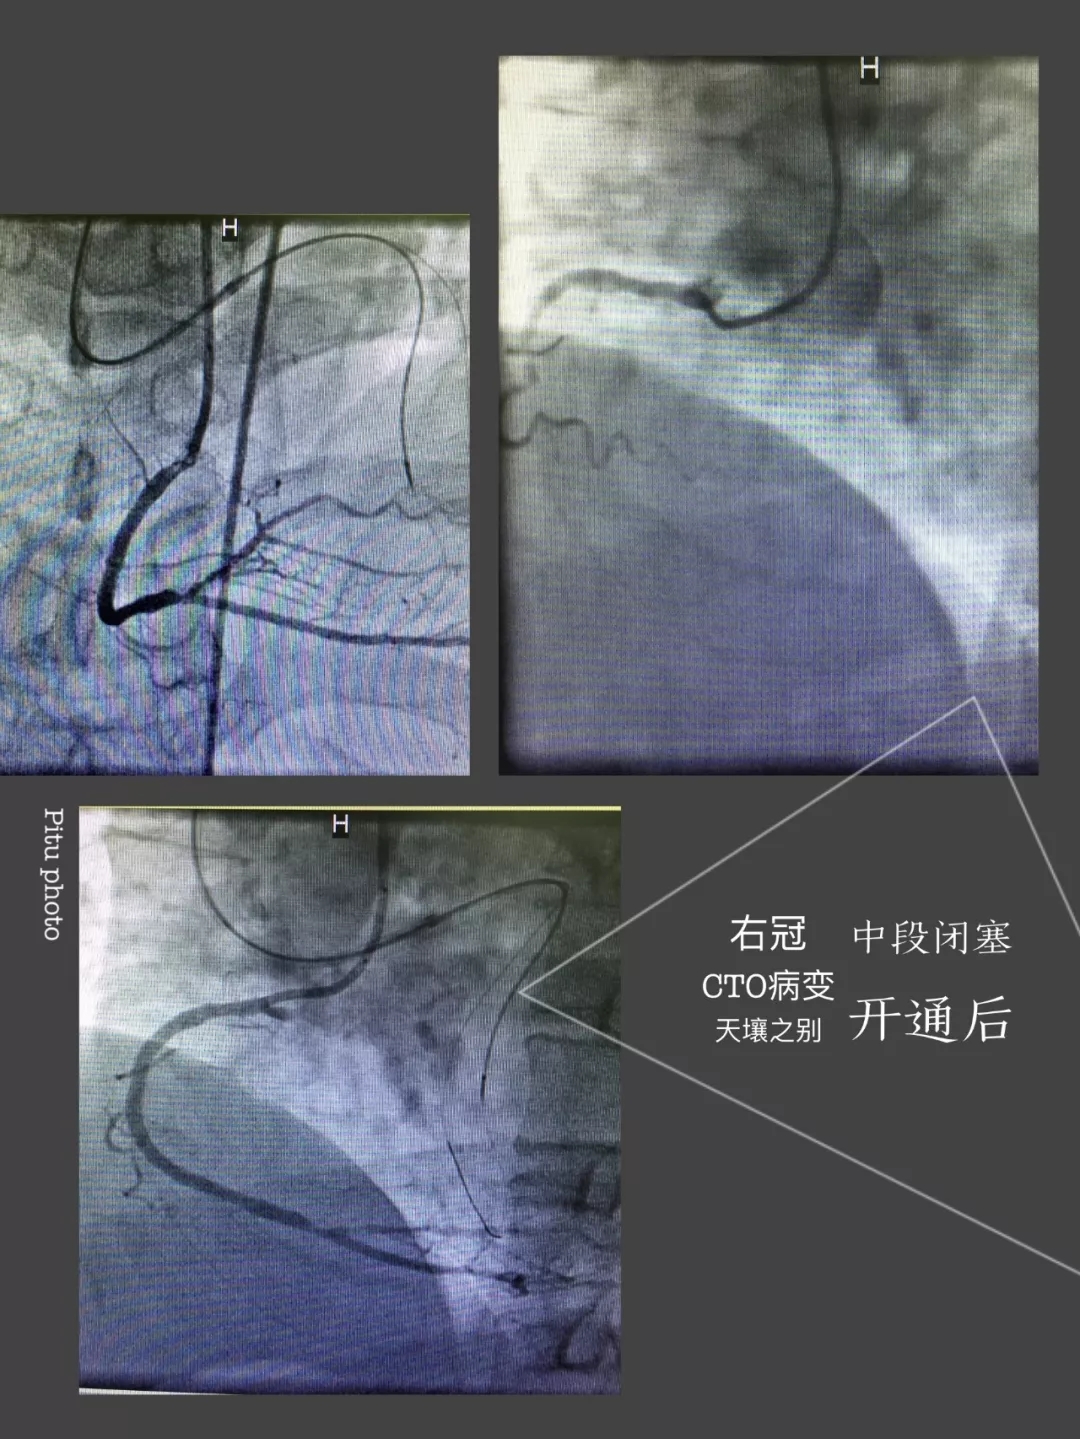

心内三完成男同视频 首例逆向开通冠脉CTO病变